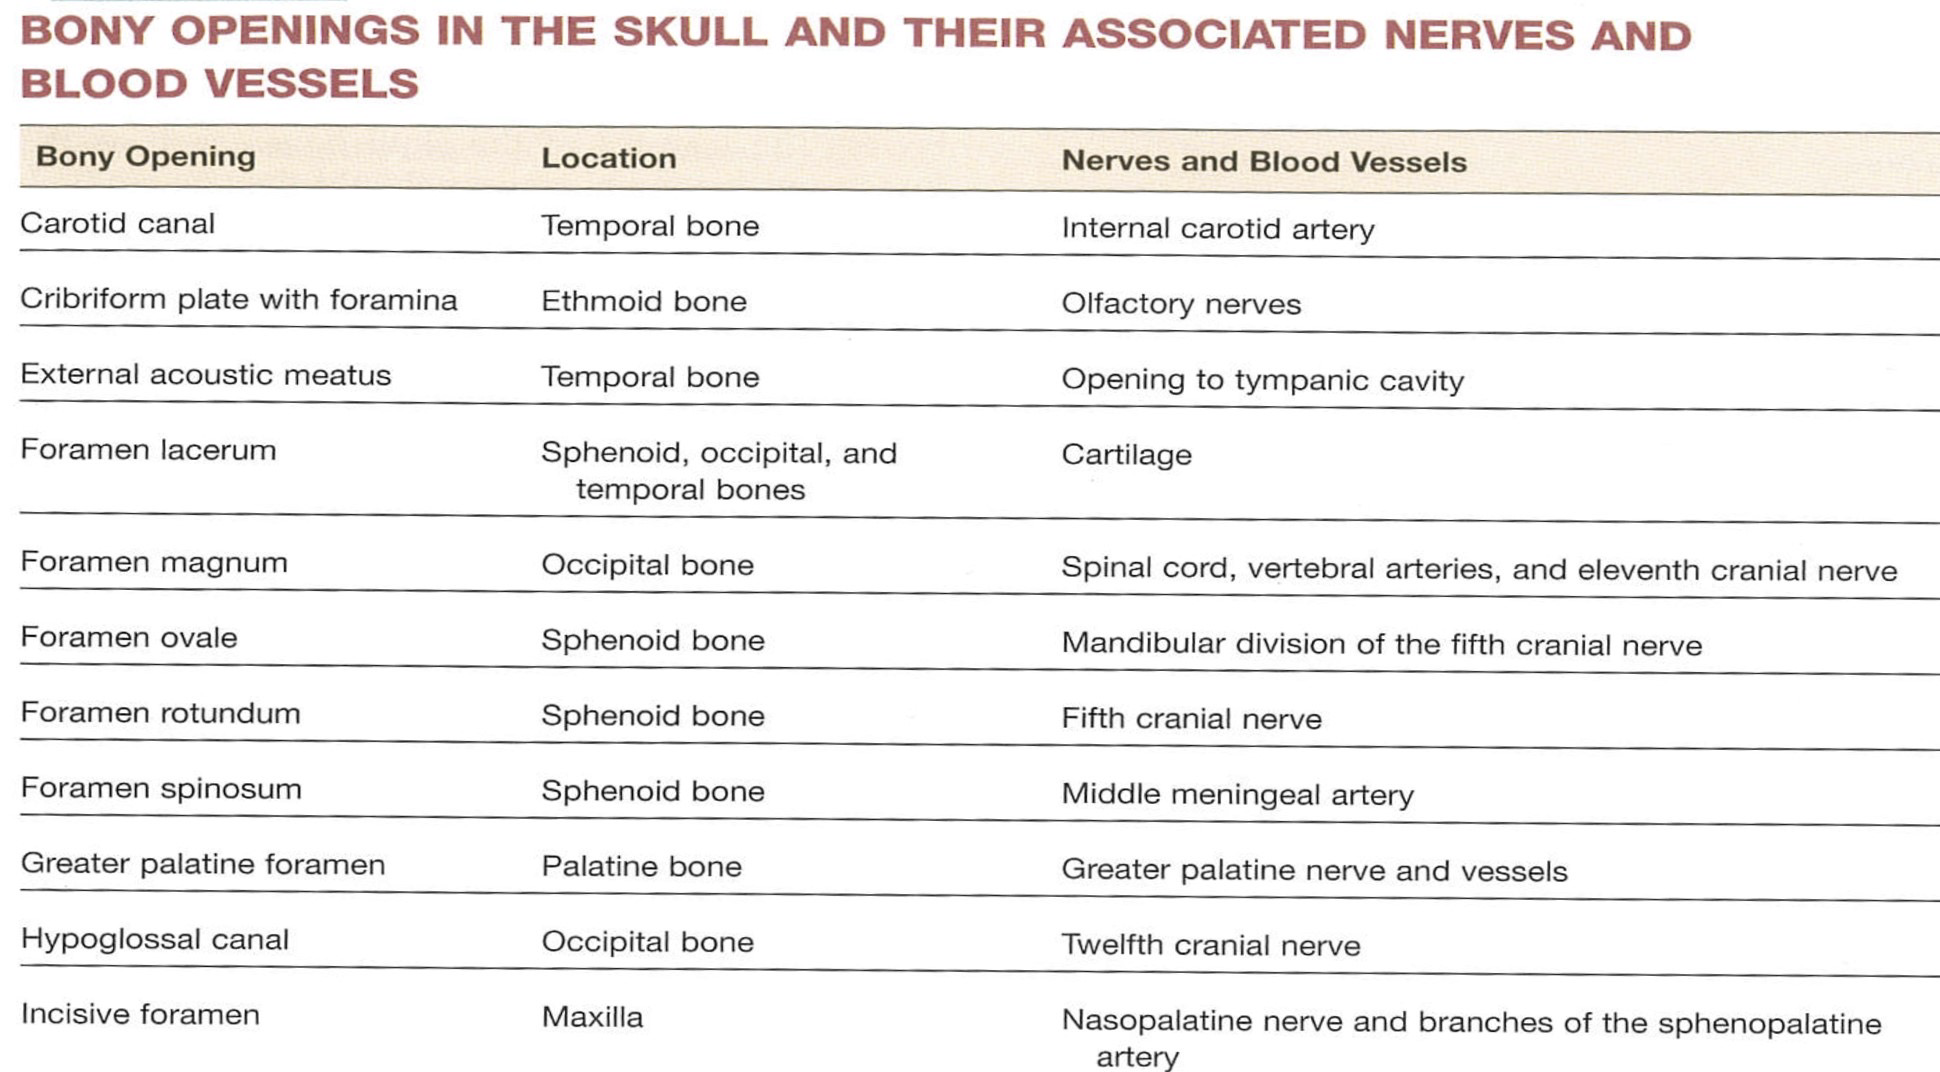

| CN | Origin | foramen |

|---|---|---|

| I | 嗅球 | cribriform plate |

| II | Optic Chiasma | optic canal |

| III, IV | Midbrain | sup orbital fissure |

| V1, VI | pons | |

| V2 | foramen rotundum | |

| V3 | foramen ovale | |

| VII | Internal coustic meatus | |

| VIII | Pons, Medulla 之間 | |

| IX, X, XI | Medulla | jugular foramen |

| XII | Hypoglossal canal |

Sphenoid bone

Foramen rotundum

Foramen ovale

Foramen spinosum

Foramen lacerum (破裂孔)

Optic canal

Sup. orbital fissure

Temporal bone

- Carotid canal

- Ext. acoustic meatus

- Int. acoustic meatus

- CN VII, VIII

- Jugular foramen

- int. jugular v.

- CN IX, X, XI

- Stylomastoid foramen

Occipital bone

- Hypoglossal canal

- CN XII

- Foramen magnum

- Spinal cord

- Vertebral a.

- CN XI

- Jugular foramen